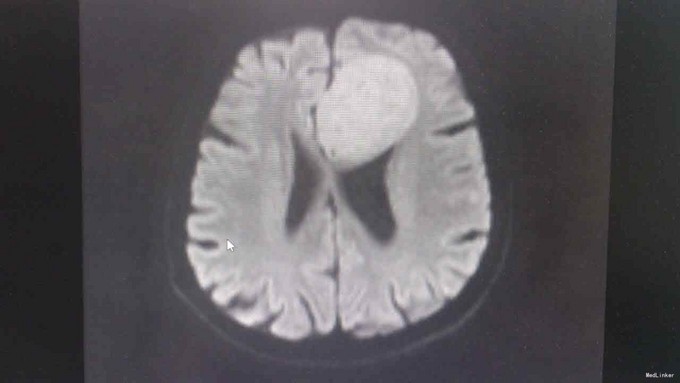

T:37℃,R: 20次/分,P:84次/分,BP:122/88mmHg。发育正常,营养中等,自主体位,步态平稳,表情自如,神志清楚,对答切题,查体合作。皮肤粘膜未见苍白、黄染,未见皮疹,无皮下出血点,无伤口。全身浅表淋巴结未扪及肿大。头颅无畸形。眉毛无脱落,眼睑无水肿、下垂、倒睫,睑结膜无苍白、充血,球结膜无充血、水肿,巩膜无黄染,角膜透明,眼球活动灵活,无凸出、凹陷、震颤、运动障碍,双侧瞳孔等大等圆,直径约3mm,对光反射灵敏,集合反射正常,左眼不能正常闭合。耳廓正常,无畸形,鼻部外形无异常,口唇红润,口腔粘膜未见出血点及溃疡,伸舌左偏,咽部无充血,扁桃体无肿大。颈软,无抵抗,颈静脉无充盈,肝颈静脉回流征(-),气管居中,甲状腺不大。胸廓对称无畸形、无局部膨隆或凹陷。呼吸平稳,节律规则。双侧呼吸动度对称。双肺部叩诊清音。双肺呼吸音清,未闻及干湿性啰音。心界不大,心率84次/分,律齐,各瓣膜区未闻及病理性杂音。腹平软,未及压痛,未及反跳痛,腹部未扪及包块,肝右肋下、剑突下未及,脾未触及,胆囊未触及,Murphy征(-)。移动性浊音阴性,肠鸣音正常,约4次/分。脊柱四肢无异常。生理反射存在,病理反射未引出。 专科检查:计算力、定向力、记忆力正常,双侧瞳孔等大等圆,直径约 4mm,对光反射灵敏,辐辏反射正常,眼球运动无受限,左侧眼睛不能正常闭合,左侧额纹消失,左侧鼻唇沟变浅,伸舌左偏,鼓腮无漏气,双上肢肌力5级,双下肢肌力5级,生理反射存在,病理反射未引出。 相关检查:血常规、大便常规、肝功能、凝血四项、离子四项、心肌酶、血脂四项、肾功能、肿瘤二项未见明显异常。 头颅增强MR1.左侧额叶大脑镰旁见团块状异常信号影,考虑脑膜瘤;2.双侧辐射冠区缺血灶;3.轻度脑萎缩。 肝胆脾胰B超、泌尿系B超未见异常。胸片示:1.双肺纹理稍增多、增粗,请结合临床;2.右上纵隔增宽,建议必要时CT检查。

诊断:脑膜瘤 治疗:甘露醇、地塞米松降颅压,择期手术治疗。